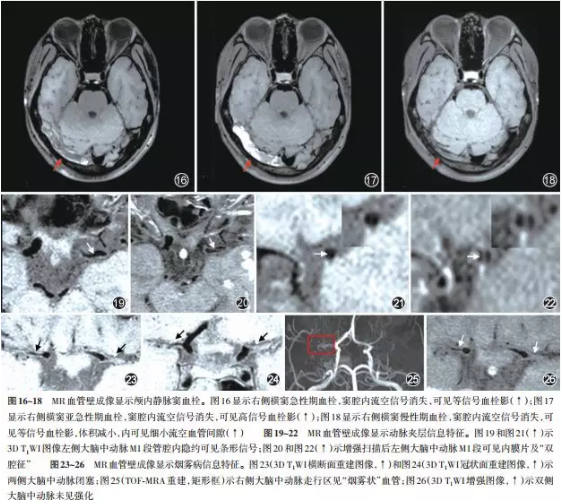

在中华放射学杂志发表了《颅内MR血管壁成像技术与应用中国专家共识》,推荐了颅内动脉成像技术方案,提供了图像质量控制和可重复性原则和颅内动静脉疾病的影像判读方法,同时,归纳总结了当前颅内磁共振管壁成像技术在颅内动脉粥样硬化、夹层、中枢神经系统血管炎、烟雾病和可逆性血管综合症等动脉血管壁病变和静脉血栓方面的临床应用(图3)。

图3 颅内MR管壁成像的临床应用

通过应用优化的T1-VISTA(西门子称为SPACE)序列对症状性颅内动脉狭窄患者的颅内动脉管壁进行成像研究发现,在158例患者中,导致颅内动脉狭窄的病因依次为动脉粥样硬化(82.3%)、烟雾病(8.8%)、动脉夹层(3.2%)、血管炎(0.6%)及其他原因不明疾病(5.1%)(图4)。本研究还发现动脉粥样硬化患者的低密度脂蛋白(2.8±1.1 mmol/L vs. 2.3±0.6 mmol/L, p = 0.022)和总胆固醇(4.4±1.4 mmol/L vs. 3.6±1.3 mmol/L, p = 0.019)水平显著高于非动脉粥样硬化患者。图5为颅内动脉粥样硬化、烟雾病、动脉夹层和血管炎患者的磁共振管壁特征。该研究结果提示,颅内动脉粥样硬化是导致国人症状性颅内动脉狭窄的最主要原因,其他非动脉粥样硬化疾病依次为烟雾病、夹层、血管炎和原因不明疾病。与非动脉粥样硬化性疾病相比,动脉粥样硬化患者表现为较高的低密度脂蛋白和总胆固醇水平。

图5 颅内动脉粥样硬化、烟雾病、动脉夹层和血管炎的磁共振影像特征

图A和B 为颅内动脉粥样硬化示例图,TOF-MRA可见右侧大脑中动脉狭窄(A,白箭),TI-VISTA图像可见右侧大脑中动脉偏心性管壁增厚(B,白箭)。图C和D为烟雾病示例图,TOF MRA可见双侧颈内动脉终末段重度狭窄闭塞(C,白箭),T1-VISTA提示右侧大脑中动脉近端管腔狭窄(D,白箭),走行区见多发侧枝血管形成(D,箭头)。图E和F为夹层示例图,TOF-MRA可见左侧大脑中动脉狭窄(E,白箭),TI-VISTA可见左侧大脑中动脉撕裂内膜片(F,白箭)。图G和H为血管炎示例图,TOF-MRA可见双侧大脑中动脉多发狭窄(G,白箭),TI-VISTA示左侧大脑中动脉向心性管壁增厚,并呈明显强化(H,白箭)。